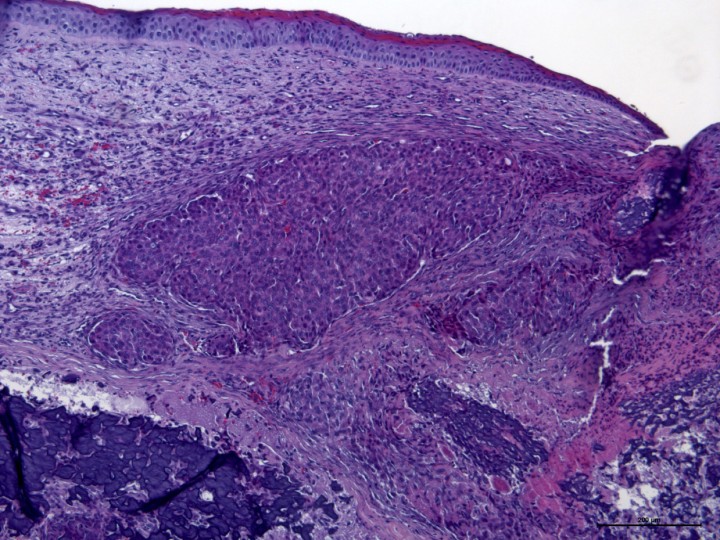

En la disección del globo ocular, las estructuras intraoculares se hallaban ocupadas por tejido calcificado no diferenciable (Fig. 6). El examen histopatológico evidenció la existencia de una proliferación neoplásica mesenquimatosa, moderadamente celular que crecía de forma infiltrativa y ocupando el vítreo, las cámaras anterior y posterior, y reemplazaba la coroides, atravesando la esclera y alcanzando la conjuntiva en la zona del limbo (Fig. 7). Las células neoplásicas crecían en trabéculas y, multifocalmente, de forma más sólida en paquetes densos sobre el estroma fibrovascular, produciendo abundante matriz osteoide que se mineralizaba de forma difusa, con osificación de las mismas, y con lagunas y osteocitos evidentes. La morfología de estas células era poligonal y fusiforme (10-15 μm) con bordes pobremente definidos. El citoplasma era de tamaño variable, eosinófilo homogéneo y con restos de matriz osteoide en algunas de las células. El núcleo era central, de gran tamaño y redondeado con cromatina finamente granular y un nucleolo eosinófilo evidente. El grado de anisocitosis y anisocariosis era moderado y el índice mitótico elevado (2-8 mitosis/40x), siendo algunas de las mitosis aberrantes (Figs. 8 y 9). Algunas células eran bi y trinucleadas. Se observaron extensas áreas de necrosis de las células neoplásicas. Se realizó tinción de inmunoperoxidasa para vimentina con resultado positivo (Fig. 10). La histopatología concluyó un diagnóstico de osteosarcoma ocular y signos de queratitis ulcerativa difusa subaguda grave.

<p>Histopatología. Córnea invadida por un crecimiento sólido e infiltrativo de células neoplásicas que substituyen parcialmente el estroma corneal. El epitelio corneal presenta una marcada hiperqueratosis. H&E (x10).</p>

Figura 7

Histopatología. Córnea invadida por un crecimiento sólido e infiltrativo de células neoplásicas que substituyen parcialmente el estroma corneal. El epitelio corneal presenta una marcada hiperqueratosis. H&E (x10).